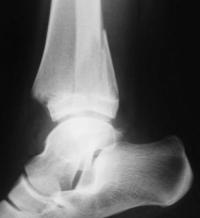

Les décollements épiphysaires Salter 4

- Trait de fracture métaphyso-épiphysaire traversant le cartilage de croissance : atteinte de la zone germinative du cartilage de croissance et fracture articulaire.

- Risque d’épiphysiodèse et d’arthrose

- Diagnostic : radiographie de la cheville de face et de profil

- Forme particulière : la fracture de Mac Farland : fracture de la malléole interne L’atteinte métaphysaire peut être une simple communition mais le risque d’épiphysiodèse reste élevé Fait suite à un mécanisme en adduction ou de cisaillement En cas de fracture du dôme astragalien associée (à rechercher attentivement), mécanisme de compression : risque d’épiphysiodèse augmenté

- Exemples…